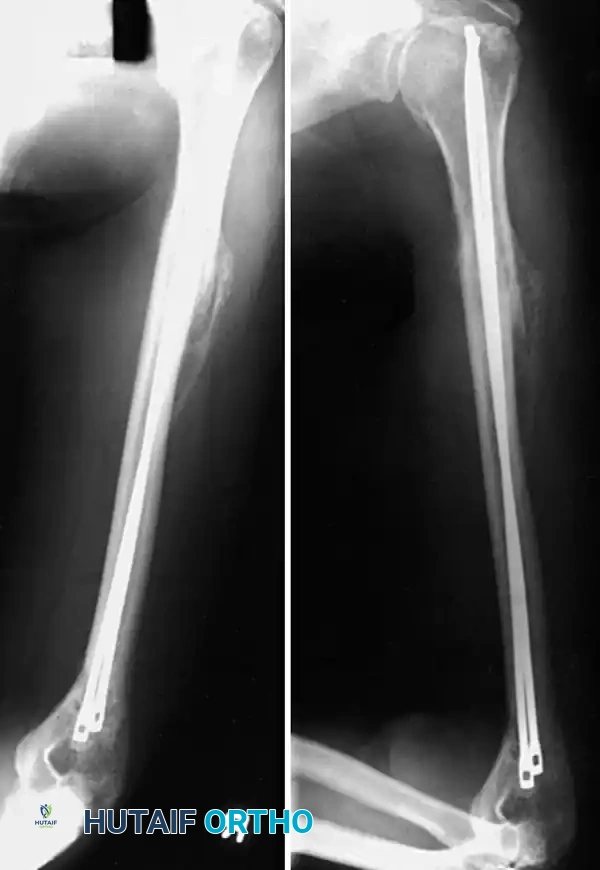

Fig. 54-28 Anterior plating of humeral shaft fracture with limited-contact dynamic compression plate.

Fig. 54-30 A, Oblique humeral shaft fracture. B, After provisional reduction with lag screw and fixation with plate and screws.

Fig. 54-31 A, Segmental shaft fracture with extension into proximal humerus. B and C, Long plate used to obtain secure fixation.